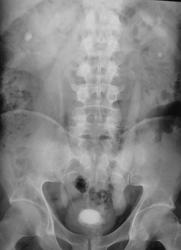

Пациент направлен на обзорную рентгенографию области почек и мочевыводящих путей.

Множественные конкременты МПС: слева в проекции нижней группы, справа скорее всего в средней группе и, конечно, в мочевом пузыре

Самое интересное то, что два дня тому пациенту было сделано УЗИ и было выставлено "объёмное образование мочевого пузыря" (опухоль), а перед этим, что и послужио поводом УЗИ, пациент хорошо "крованул".

Кровить могут и камни, точнее то, что они раздражают. При такой картине явлений всякого рода хронического воспаления-выше крыши, а при УЗИ скорее всего не отдифференцировали стенку пузыря и прилипший камень, но... Иногда на выделительных урограммах прекрасно видные краевые дефекты стенок за счет маленьких стелющихся опухолей, эти кровят будь здоров. Хотя, честно, на этом обзоре стенки четкие, ровные.

А с чем связано расширение левого мочеточника. Не думаю, что на УЗИ не заметитли камень. Он даёт такую эхотень, при его размерах, что спутать с образованием нельзя. Да и при смене положения должен перемещаться.

Фрагменты с увеличением.